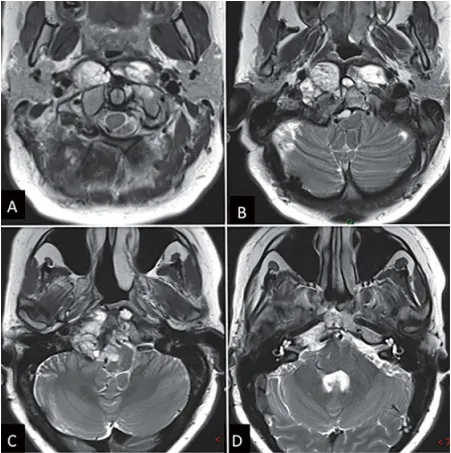

這很有可能是一個(gè)斜坡嵴索瘤,現(xiàn)在有332633mm這么大,已經(jīng)侵襲左側(cè)海綿竇,導(dǎo)致垂體移位、垂體柄歪斜,但手術(shù)風(fēng)險(xiǎn)很大,家屬要慎重考慮。 幾月前,小海的父母被醫(yī)生告知了這一噩耗。盡管...